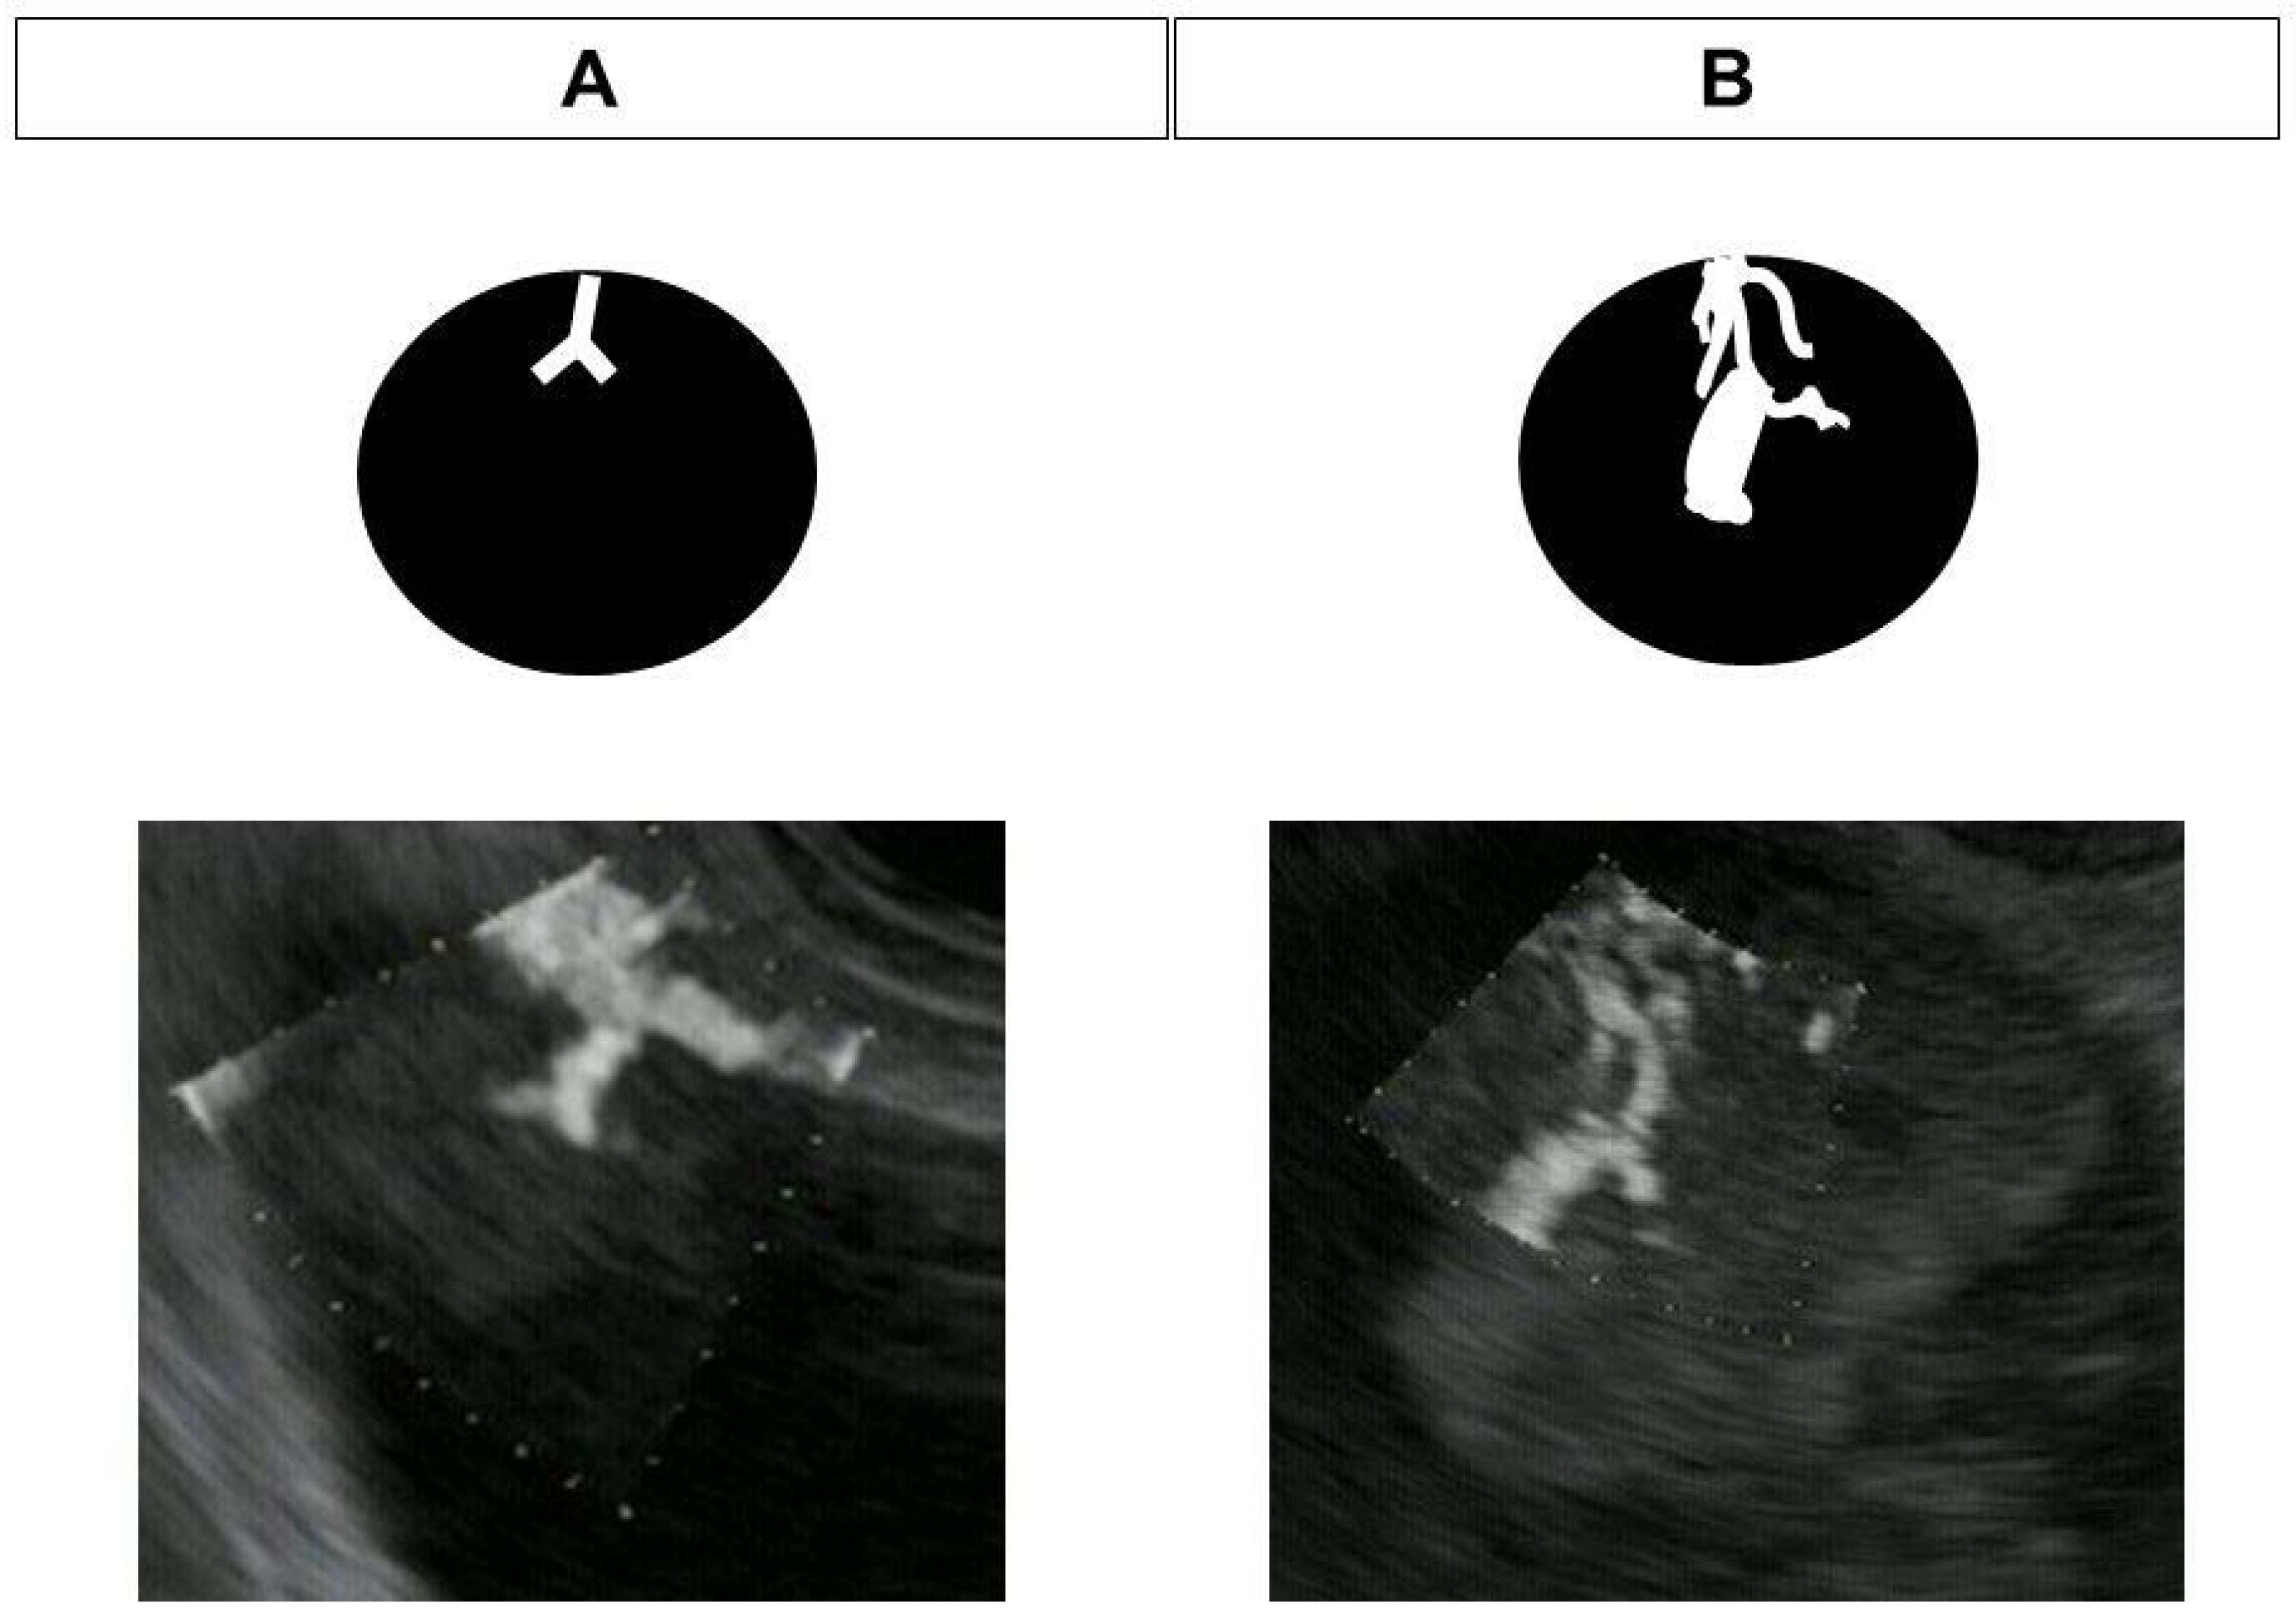

2.4. DFI-EUS

- Yamashita, Y.; Yoshikawa, T.; Yamazaki, H.; Kawaji, Y.; Tamura, T.; Hatamaru, K.; Itonaga, M.; Ashida, R.; Ida, Y.; Maekita, T.; et al. A Novel Endoscopic Ultrasonography Imaging Technique for Depicting Microcirculation in Pancreatobiliary Lesions without the Need for Contrast-Enhancement: A Prospective Exploratory Study. Diagnostics 2021, 11, 2018. [Google Scholar] [CrossRef]

- Yamashita, Y.; Yoshikawa, T.; Kawaji, Y.; Tamura, T.; Hatamaru, K.; Itonaga, M.; Ida, Y.; Maekita, T.; Iguchi, M.; Murata, S.I.; et al. Novel endoscopic ultrasonography imaging technique for visualizing microcirculation without contrast enhancement in subepithelial lesions: Prospective study. Dig. Endosc. 2021, 33, 955–961. [Google Scholar] [CrossRef] [PubMed]